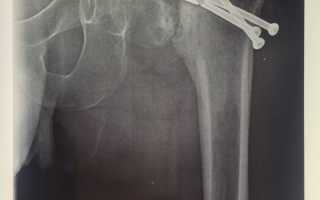

Ложный сустав при переломе шейки бедра лечение